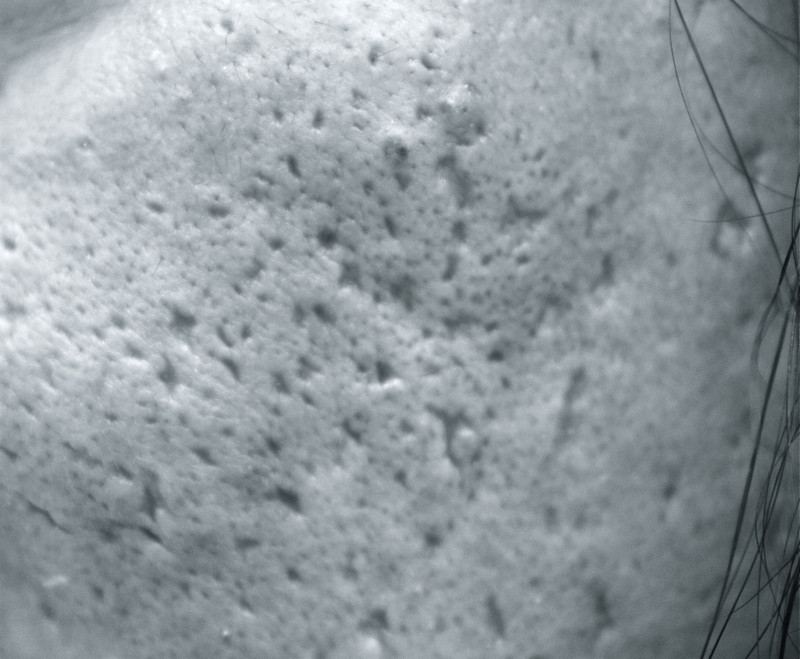

すなわち、ニキビ瘢痕(下写真)には予防しかないということなんです